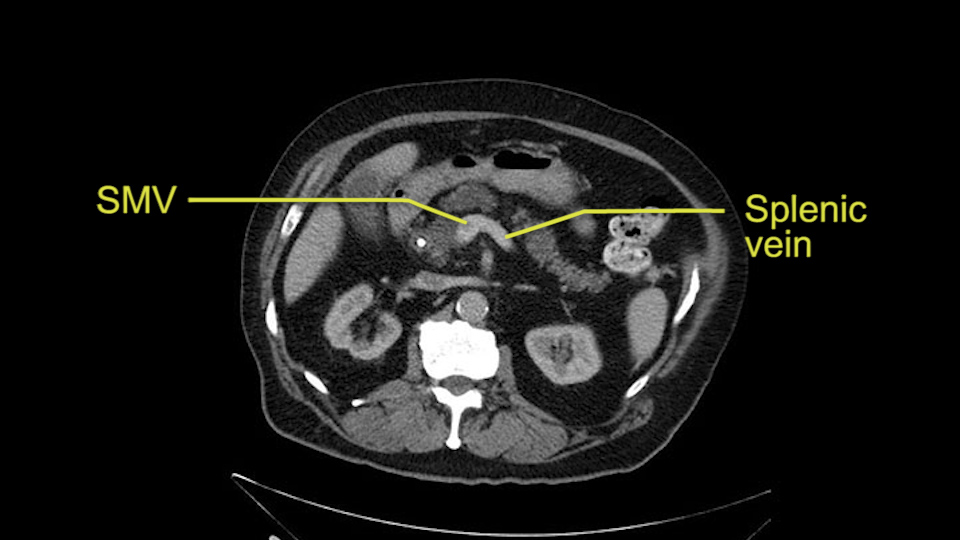

The next item that I would look at: the issue would be the vessels and usually start at the portal vein, watch the portal vein, follow it down, down-down-down to the neck of the pancreas - which is here - and there’s no impingement by tumor, which is great. The SMV and the splenic vein, which is here. The splenic vein junction is normal, which is great.

The other thing I look at is the gastroepeiploic arcade- which is this thing here- which is where the gastroepeiploic vein joins the portal vein. I call it the gateway to the neck of the pancreas because you pretty much have to divide it to get to the neck. The middle colic vein usually drains either into it or nearby. I think we’re seeing it here. Again,that can be divided and I usually divide those two and it helps me get under the neck. Again, there’s no issues here with the tumor so it’s nice from that perspective. If I was concerned about the vein, which I’m not here, I would go to the coronal view. It’s a nice way to look at the vein on just a couple of cuts and you can see a beautiful view of it here. There’s the portal vein, there’s the head of the pancreas. There’s the tumor. It’s a little closer here than it looks on the other one. I doubt it’s involved. If it’s touching, it may not be invading it but even if it was, it's a short segment. Anyways, there’s the SMV there’s the splenic vein, and everything looks good. You can see the stent. I ignore the stent. It’s the most dramatic looking thing in the picture but it’s actually the least important.